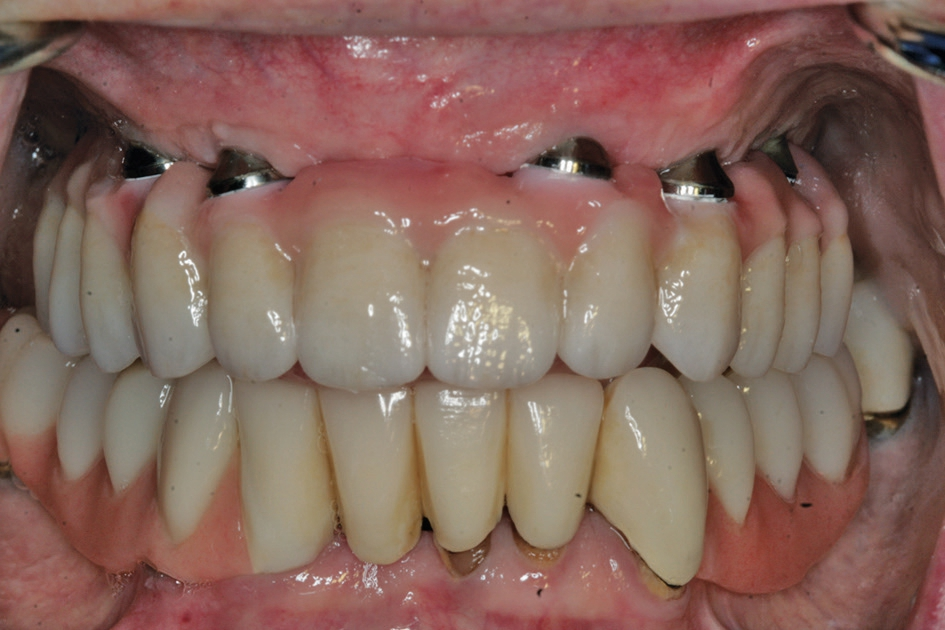

Nach einer initialen Abformung können vom Zahntechniker die optimalen Aufbauten nach der physiologischen Aufstellung und Wachseinprobe ausgewählt werden (Abb. 7 bis 9). Diese werden dann in die Implantate eingeschraubt und verbleiben dort, ohne dass sie wieder entnommen werden. Durch die Auswahl der Aufbauten vom Zahntechniker kann dort auch gleich eine Verblockung vorbereitet werden, mit der es möglich ist, die endgültig erreichte Position der angulierten Aufbauten direkt in das Labor zu übertragen. Somit stellt das Meistermodell eine identische Kopie der klinischen Situation dar. Dies ist notwendig, damit im Rahmen von CAD/CAM-Verfahren Gerüste für die weitere prothetische Versorgung gefräst werden [14]. Je nach Umsetzung der patientenindividuellen Aufstellung kann die definitive Versorgung hergestellt werden. Dort bestehen heute die Möglichkeiten der CAD/CAM-Technologien mit einem Titan- oder einem Keramikgerüst zur Verfügung. Sofern sich kein absolut passgenaues Gerüst erreichen lässt, kann dies durch eine Klebebasis kompensiert werden [5]. Dies wird in der Regel bei reinen Zirkonoxidgerüsten erforderlich. Im weiteren Ablauf kann die individuelle Charakterisierung der Vestibulärflächen und des Weichgewebsübergang erreicht werden (Abb. 10 bis 14).

Nachteilig gerade bei einer geringen apikalen Basis und der Notwendigkeit, die Osteotomie und damit auch die Implantate zentripedal stark zu neigen, zeigt sich beim Bone Splitting der relative vertikale Verlust, da die Lamelle nach vestibulär mobilisiert wird und dadurch durch den Winkel eine vertikale Reduzierung erreicht wird. Dies kann aber je nach Lachlinie des Patienten durch eine Gestaltung der Suprakonstruktion mit rosaeingefärbter Keramik oder Kunststoff kompensiert werden. Durch die Möglichkeiten der modernen Prothetik kann auch bei einer vermeintlich ungünstigen Implantatpositionierung mithilfe von unterschiedlich stark angulierten Abutments eine Abdrucknahme auf Schleimhautniveau erreicht werden, die die Anfertigung einer präzisen Implantatversorgung ermöglicht.